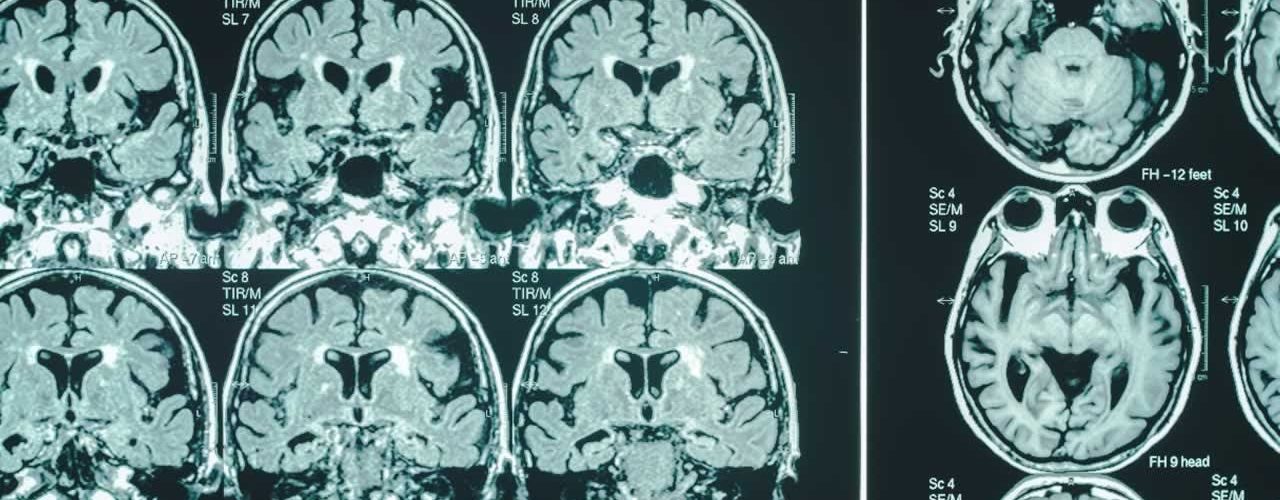

After thirty years of research as a neurologist and neuroscientist, Dr. Dale Bredesen wrote “The End of Alzheimer’s.” See more about The Bredesen ProtocolTM